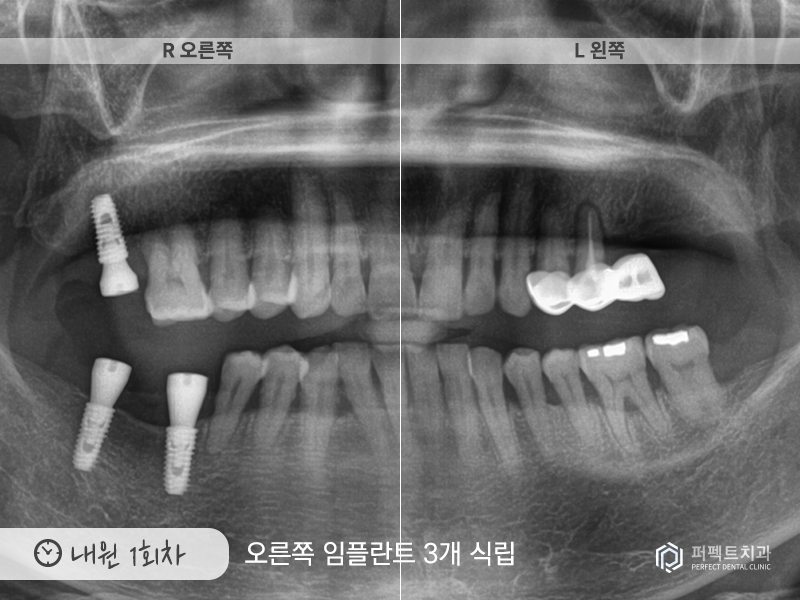

내원 1회

처음 내원 하신 날에는 오른쪽 어금니 임플란트 3개를 식립하였고